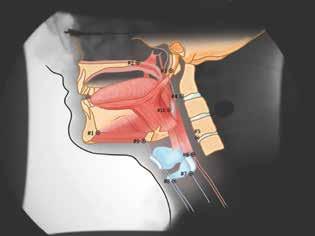

Patient-specific CASM allows for visualization of swallowing mechanics (hyoid movement, laryngeal elevation, tongue base retraction, and pharyngeal shortening) using eigenvectors that characterize the relative contribution of each element of swallowing mechanics. CASM is a multivariate morphometric analysis of coordinates that is used to map muscle groups that underlie oropharyngeal swallow mechanics represented in the lateral-view modified barium swallow (MBS) imaging at 30 frames per second (figure 1).4,5

Figure 1. Coordinates are used to map the swallowing mechanics in the suprahyoid muscle group (#9 to the mandible [vectors #1 to #3]) and in the thyrohyoid (#8 to #9), the stylopharyngeus (#7 to #3), the palatopharyngeus (#6 to #2), and the styloglossus and hyoglossus (#10 to #3) muscles. It also shows the movement of three skeletal levers, including the skull base (#2 to #3), the mandible (#1 to #3), and vertebrae (#3, #4, and #5). Illustrations courtesy of Mark A. Ellis, MD, and William G. Pearson Jr., PhD.

Figure 2. Patient 1. A: Vectors in nonsurgical controls show normal swallowing mechanics. B: Vectors in patient 1 demonstrate an absent pharyngeal shortening (vector #6) and an aberrant (superior vs. posterior) tongue base retraction (#10). (OT = oral transport; P = pharyngeal swallowing; 1 = patient 1).

and an aberrant (superior vs. posterior) tongue base movement (vector #10).

An MBS study performed 2 months after surgery revealed a PAS score of 2. Findings were otherwise unremarkable, including complete velopharyngeal valve closure. Patient-specific CASM was performed on the MBS imaging. When visually compared with normative values for CASM in nonsurgical controls (figure 3, A), our patient’s analysis (figure 3, B) demonstrated an absent pharyngeal shortening (vector #6) and an aberrant (superior vs. posterior) tongue base retraction (vector #10).

We used computational analysis to examine swallowing mechanics and structural changes in postoperative OSA surgery patients. It is interesting that our 2 patients demonstrated similar changes in swallowing mechanics—namely the absence of pharyngeal shortening and the presence of aberrant movement of the tongue base in the superior vs. posterior direction compared with swallowing mechanics of nonsurgical patients. There were no significant differences in laryngeal elevation and hyoid excursion between our 2 patients and normal controls.